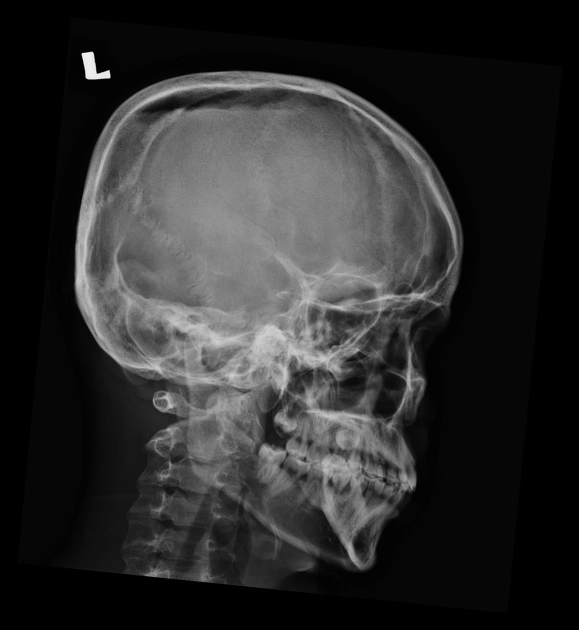

Gãy sương sọ (Skull fractures)